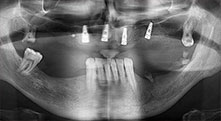

Le Professeur Emanuel Bratu, chirurgien maxillo-facial, stomatologue et prothésiste, dirige les départements d'implantologie dans deux universités roumaines. Il dirige un hôpital privé renommé à Timisoara et c'est un chercheur internationalement connu. Dans cet entretien, le Dr Bratu explique pourquoi il pense que l’unit de chirurgie piézoélectrique Piezomed de W&H, et en particulier deux scies brevetées, sont devenus essentiels en chirurgie osseuse.

Pr Bratu : Nous utilisons couramment les instruments pour le prélèvement des blocs osseux et le clivage de la crête alvéolaire. Nous utilisons également les scies B6/B7 Piezomed pour l'ostéotomie des dents endommagées et l'extraction des implants défaillants. Bref, toutes les indications qui nécessitent des coupes profondes et propres.

Pr Bratu : Nous préférons prélever l'os sur la crête oblique externe de la mandibule postérieure, et non dans la région interforaminale. Après l'incision des tissus mous, nous utilisons les nouvelles scies pour définir la quantité d'os à prélever. De la même manière, nous les utilisons également pour la totalité de la préparation dans presque 80 % des cas. Nous avons également parfois recours à d'autres instruments piézoélectriques et, pour terminer, à un burin pour mobiliser le bloc. Nous trouvons cette technique chirurgicale très efficace.